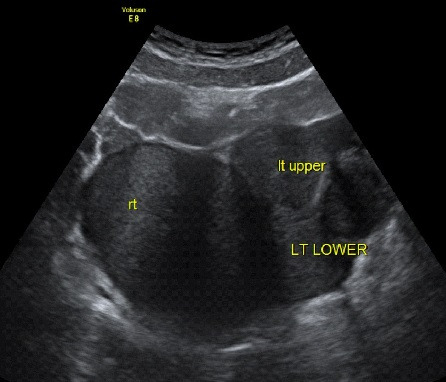

아래는 임신을 준비하는 여성들의 초음파 검사에서 관찰되는 영상입니다.

자궁근종이 있는지, 자궁 용종이 있는지, 난소에 혹이 있는지 확인할 수 있는 간편하면서도 정확도가 높은 검사입니다. 비용은 병원마다 천차만별이오니 꼭 미리 확인하고 가시기 바랍니다. 자궁근종, 자궁 용종, 난소에 자궁내막종의 여부에 따라 난임에 대한 접근방법이 바뀔 수 있어 필수적으로 시행하는 검사입니다.

여성 생식기를 보게 되며, 보는 방법에는 질식 초음파와 복식 초음파, 음순을 이용한 초음파 방법이 있습니다만, 가장 많이 이용하는 방법은 복식 초음파(Transabdominal USG)와 질식 초음파(Transvaginal USG)입니다. 쉽게 설명하면, 산모의 태아를 보듯 배를 통해서 보면 복식 초음파이고, 질(vagina), 아기가 나오는 길(산도)을 통해서 보게 되면 질식 초음파입니다.

임신하지 않은 여성이나 10~12주 이전 산모의 경우에는 태아가 작아서 질식 초음파를 이용해서 태아를 관찰하는 경우가 많습니다. 그리고 20주 이후에도 자궁경부를 확인하기 위해서 질식 초음파를 관찰할 때가 있습니다.

일반 여성 환자의 경우, 복부 초음파로 검사를 시행할 수도 있지만, 하복부 지방으로 인해서 복식 초음파가 쉽지 않을 때가 많고, 질식 초음파가 훨씬 선명하기에 질식 초음파를 사용하게 됩니다.